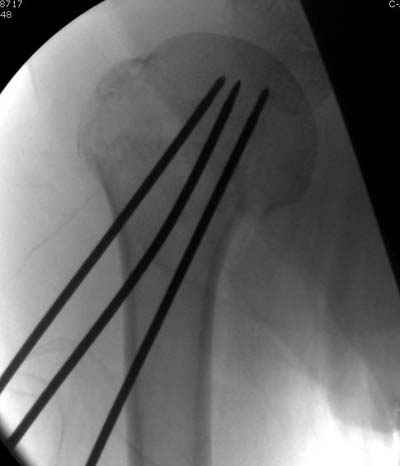

Пока я пользуюсь методикой принятой у нас (методика Сиэтла), также перкутанный спицевой метод, только сцицы 2.8 мм с резбой на конце.

Здесь случай перелома-вывиха плеча, больному 56 лет, после "дважды" закрытой неудачной репозиции, опять же ургентно взяли в операционную, после полного общего обезболивания попытались сделать репозицию, и фиксацию провели спицами.

Больной находился в повязке, примерно напоминяющей косыночную, рекомендованы движения в локтевом суставе и маятниковые движения в плече, спицы удалены в три недели (были случаи миграции)